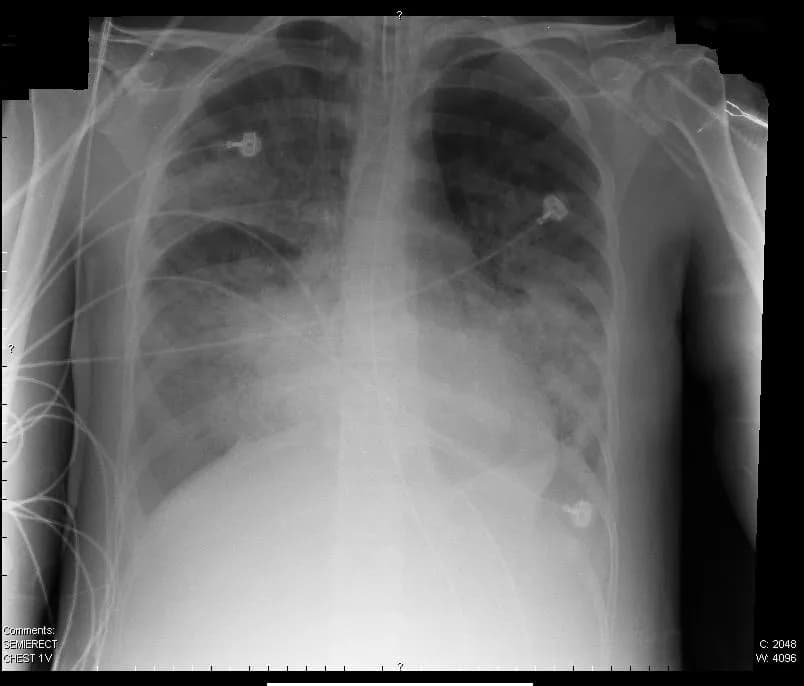

Diagnostyka opiera się głównie na badaniach gazometrycznych krwi tętniczej. Kluczowe znaczenie ma również spirometria.

Badania obrazowe, w tym RTG klatki piersiowej i tomografia komputerowa, pomagają określić przyczynę schorzenia.

Rozróżnienie między ostrą niewydolnością oddechową (J96.0) a przewlekłą niewydolnością oddechową (J96.1) wymaga dokładnej analizy parametrów gazometrycznych i objawów klinicznych. Diagnostyka powinna być kompleksowa i obejmować zarówno badania laboratoryjne, jak i obrazowe.